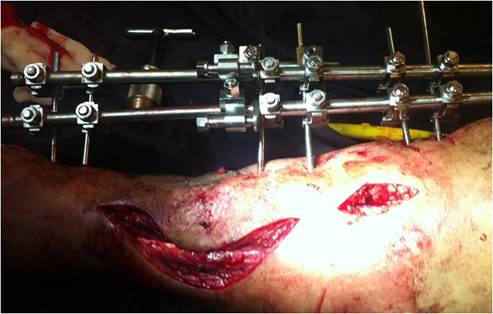

3) Osteotomía proximal o distal de tibia metafisaria según localización del defecto óseo en diferente incisión quirúrgica, la misma se puede realizar con escoplo, sierra Gigli o con mecha. Osteotomía de peroné.

4) Revisión del montaje y alineación del miembro, revisión de osteotomía.

8) Revisión del sitio de acoplamiento: al completar el transporte óseo, se realizó desbridamiento de tejido interpuesto, aplicación de injerto óseo autólogo a todos los pacientes. En algunos casos compresión interfragmentaria y en los pacientes que necesitaron realineación o el sitio de acoplamiento era defectuoso entre los fragmentos, se realizó colocación de placa bloqueada previo retiro de montaje de fijadores.

La mayoría de las lesiones se debieron a accidentes de tránsito, clasificadas como fracturas expuestas Gustilo IIIB, como expresa la literatura internacional1. Es muy importante el manejo previo de las partes blandas y la correcta resección de fragmentos óseos desvitalizados, antes de armar el montaje.